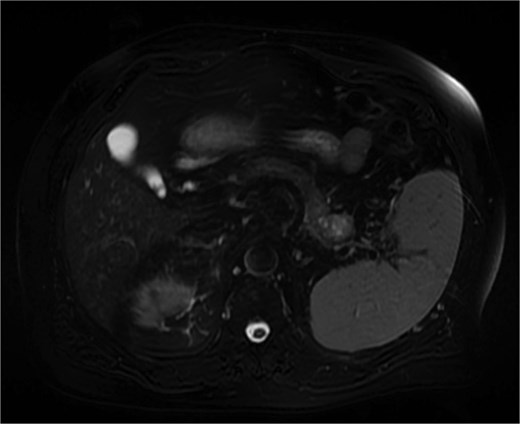

Further characterization of the pancreas using MRI revealed a 2.6 cm lesion in the pancreatic tail, best visualized during the venous phase of the scan. The lesion exhibited heterogeneous T2 signal intensity with areas of high signal but lacked diffusion restriction (Fig. 2). Postcontrast images showed peripheral rim enhancement.

MRI (venous phase) shows a 2.6 cm lesion in the pancreatic tail, exhibiting heterogeneous T2 signal intensity with areas of high signal but lacking diffusion restriction.